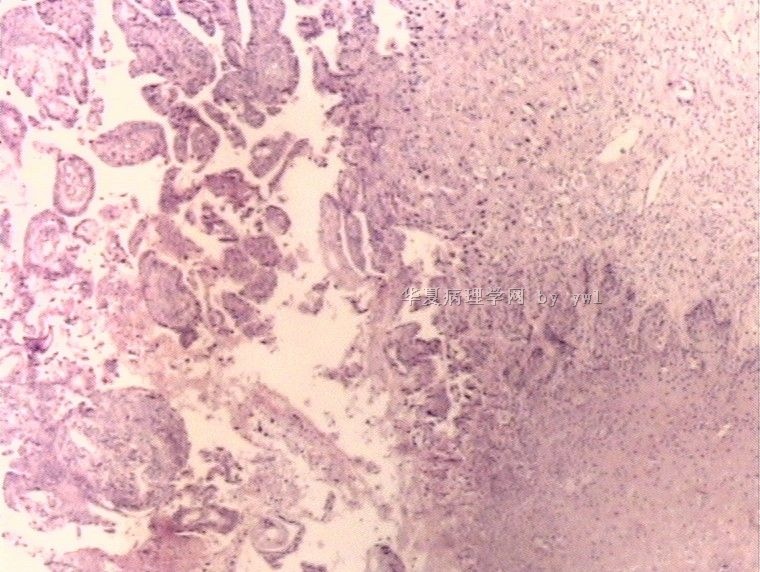

腺鳞癌?

姓    名: ××× 性别:   年龄:  39岁

标本名称:  宫颈活检

简要病史:  同房出血3次,tct HSIL

考虑:原位腺癌,小灶性区域有鳞状上皮向间质内浸润,考虑有鳞状细胞癌结构。

• 腺鳞癌?图3

图3